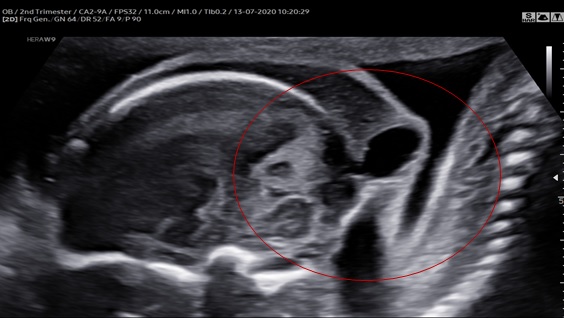

Hình 1: Mặt cắt dọc cho thấy cổ gập sau sát với cột sống và thoát vị màng não ở xương chẩm.

Hình 2: Mặt cắt ngang cho thấy thoát vị màng não, nếp gấp da gáy dày

Ca của chúng tôi có đầy đủ các đặc điểm của một Iniencephaly thể hở: thoát vị màng não, đầu cỗ ưỡn cố định ra sau, da vùng cằm liên tục với ngực, cột sống cổ biến dạng và hợp nhất một cách bất thường.